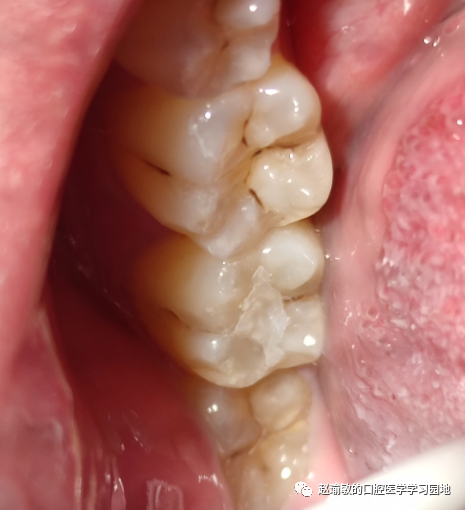

左下7颌面窝沟龋坏,颊沟处也有,已经去了龋。颌面没有去龋。